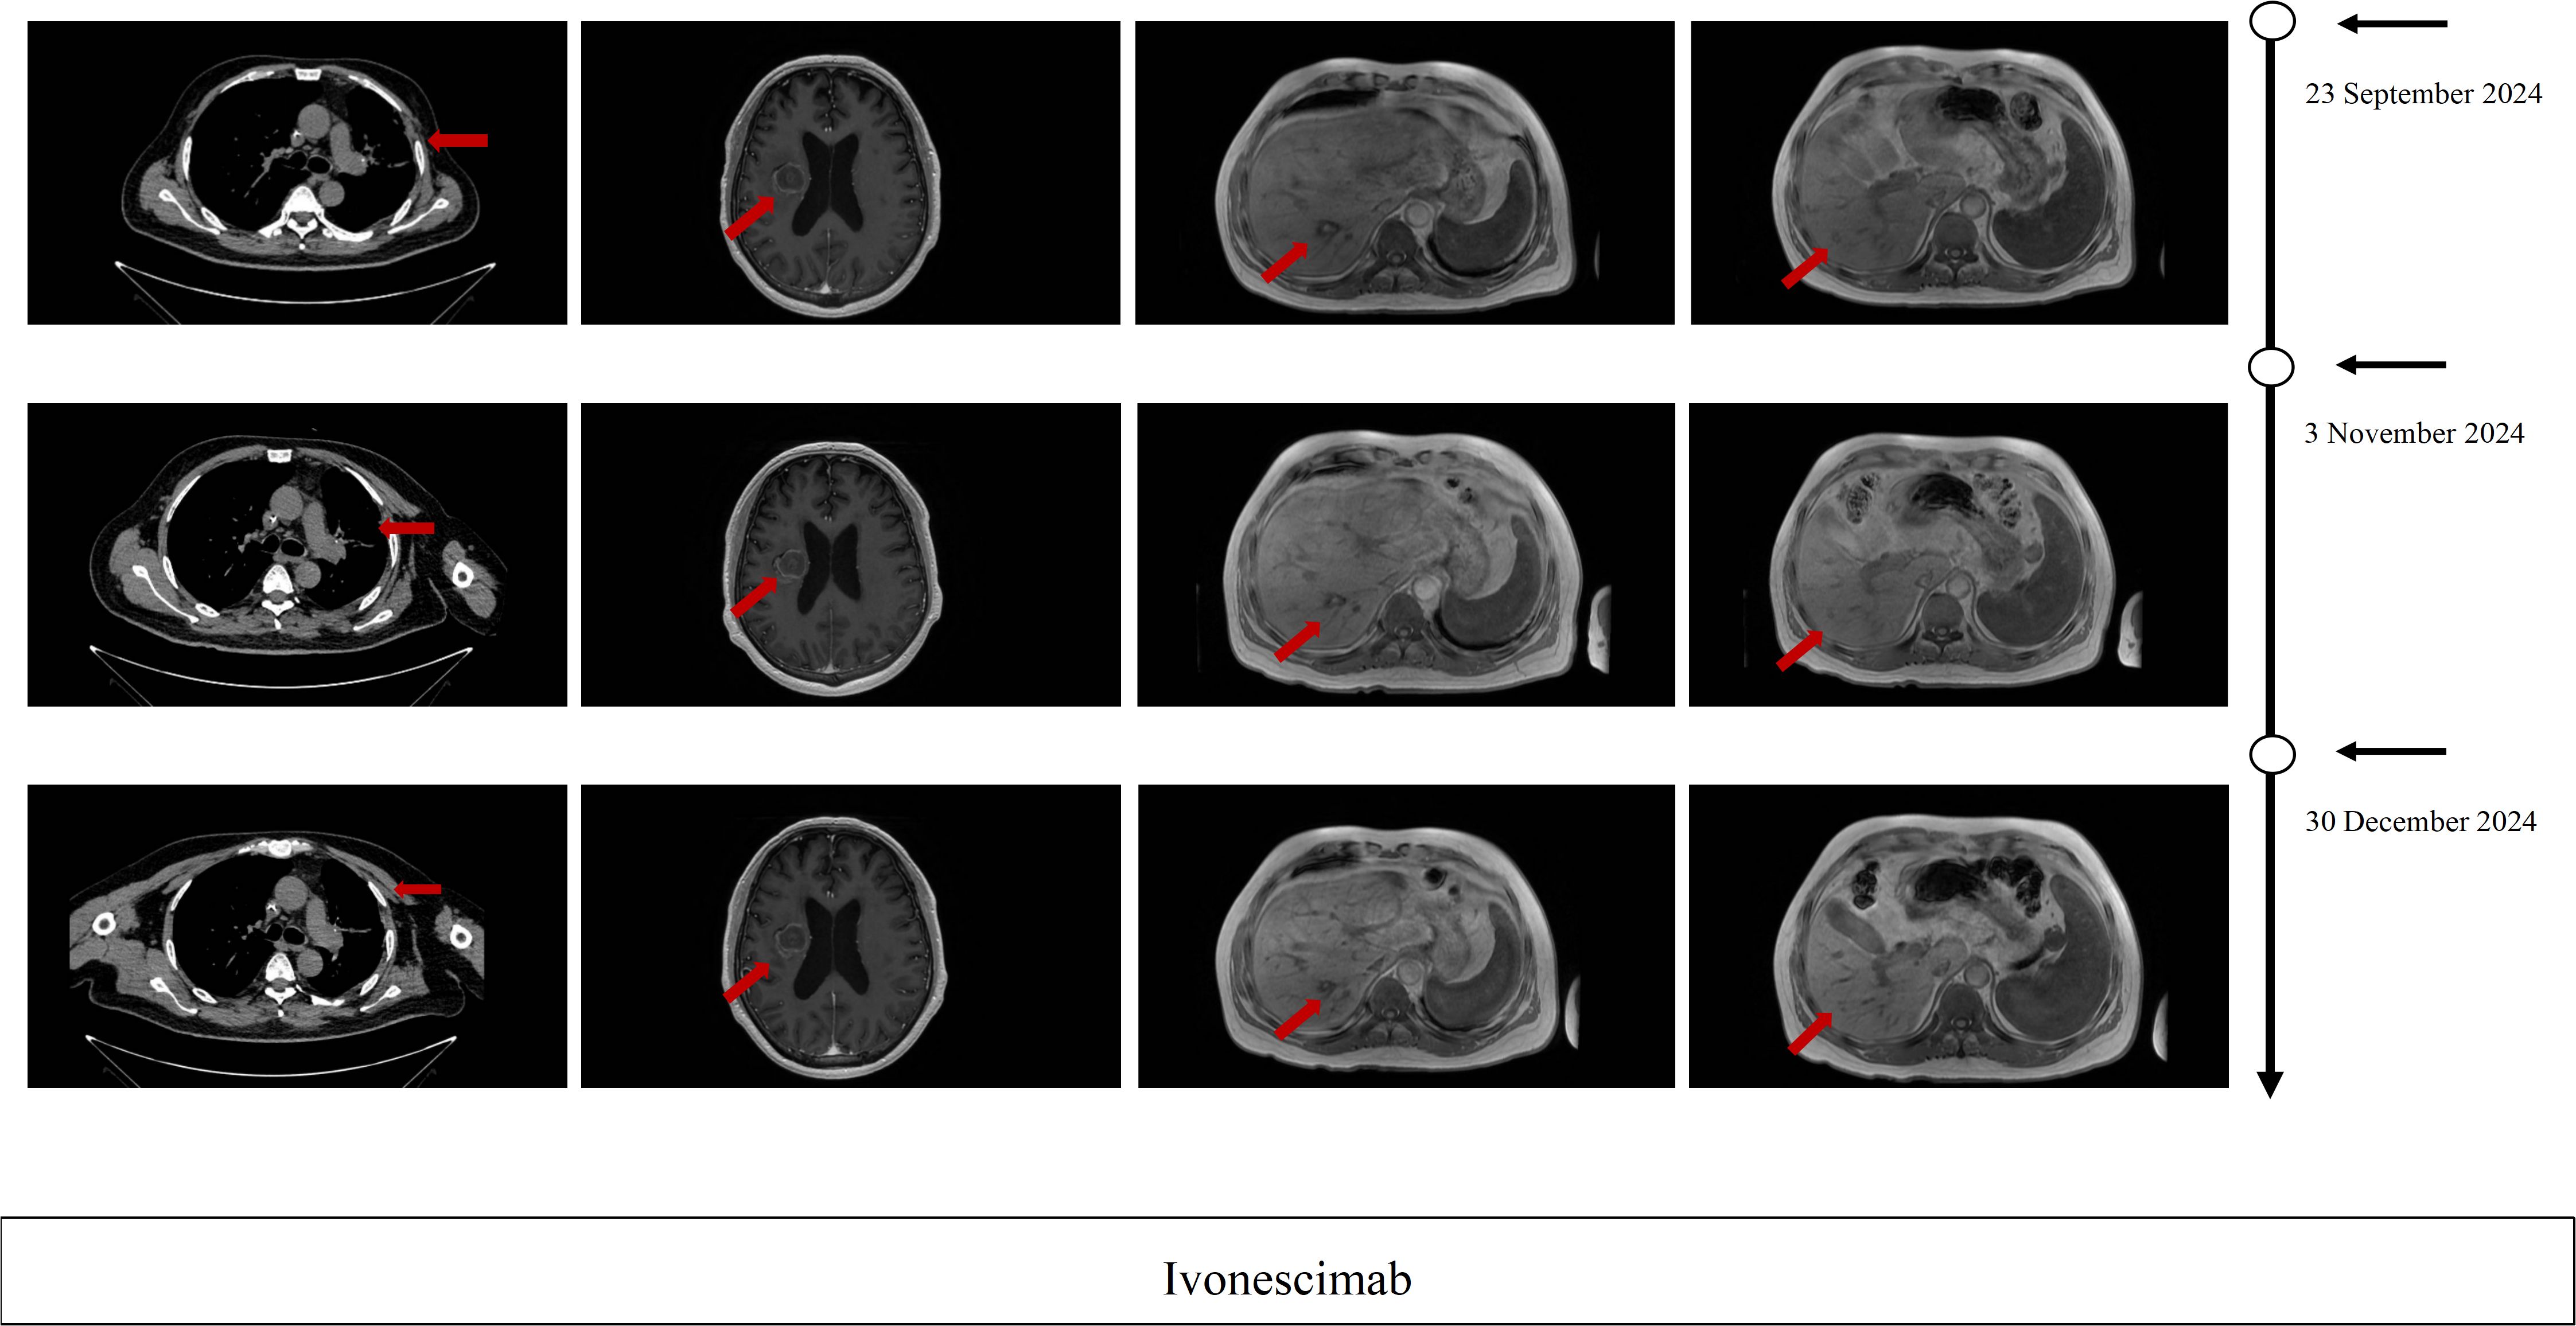

This case report describes a 51-year-old male with advanced Epidermal Growth Factor Receptor (EGFR) mutant (p.T790M and p.L858R) lung adenosquamous carcinoma who achieved a rapid partial response (PR) to ivonescimab monotherapy following progression on multi-line therapies, including third-generation EGFR-tyrosine kinase inhibitors (EGFR-TKIs), platinum-based chemotherapy, anti-angiogenic therapy, and immune checkpoint inhibitors. Despite initial responses to first-line firmonertinib-based combination therapy, progression-free survival (PFS) 13 months, the patient developed sequential resistance to subsequent regimens, including liver/brain metastases and treatment-related toxicities. After fourth-line therapy failure and severe intolerance to albumin-bound paclitaxel and bevacizumab, two cycles of ivonescimab—a first-in-class programmed cell death protein receptor-1 (PD-1)/vascular endothelial growth factor-A (VEGF-A) bispecific antibody—induced significant regression of pulmonary target lesions (PR), sustained over six cycles with minimal toxicity. This case highlights ivonescimab's dual-mechanism potential to overcome resistance in EGFR-mutant Non–small cell lung cancer (NSCLC) by concurrently alleviating PD-1-mediated immunosuppression and VEGF-driven angiogenesis. The observed efficacy in a low PD-L1 expression, tumor proportion score (TPS) 5%, tumor protein 53 (TP53)-co-mutated, and adenosquamous histology context aligns with prior clinical trial data (HARMONi-A/2), suggesting broad applicability across heterogeneous subgroups. While the rapid PR and favorable safety profile are promising, longer follow-up is required to assess durability and survival benefits. These findings underscore the need for further investigation of bispecific antibodies in precision oncology paradigms for multi-refractory EGFR-driven NSCLC.